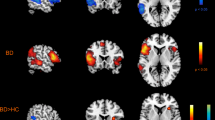

Figure 4 shows areas of white matter in which FA correlated with GCC in the case group, independent of age and sex, as determined by TBSS (TFCE-corrected p < 0.05). Correlations were found in widespread areas of white matter, including the mid-body of the corpus callosum, the cingulum and the superior longitudinal fasciculus (SLF). There were no significant correlations in the control group.

TBSS results showing areas of white matter which exhibit correlation between FA and GCC score in cases, independent of age sex and deprivation index (p < 0.05, TFCE-corrected). No significant correlations were found in controls. The white matter skeleton is shown in green with significance of positive correlations indicated by the colour bar. These are overlaid on the MNI standard template with the position of the slice in MNI space given under each slice. Labels indicate some major white matter tracts and regions. ATR anterior thalamic radiation, CC corpus callosum, EC external capsule, FMajor forceps major, FMinor forceps minor, IC internal capsule, IFOF inferior fronto-occipital fasciculus, ILF inferior longitudinal fasciculus, SLF superior longitudinal fasciculus.